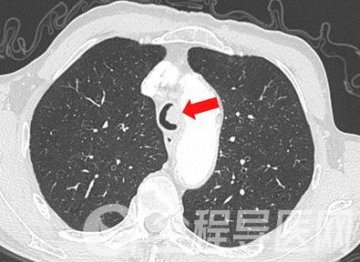

患者胸部增强CT示气管内结节状高密度影,相关气管腔变狭窄,增强扫描未示明显强化,考虑气道内良性肿瘤的可能,在崔文洁的主持下,经过科室团队详细讨论,决定对陈大爷实施全麻支气管镜下电圈套器联合氩气刀治疗腔内病变。在经过科室团队与麻醉科共同讨论评估后,制定了缜密的手术与麻醉方案及应急预案,做好充分术前准备。

刘先生因近一个月出现咳嗽、咳痰、胸闷,入住呼吸与危重症医学科三病区。胸部CT提示两肺内弥漫多发结节状、斑片状、片状密度增高影,部分实变,增强扫描未示明显强化,纵隔内及两肺门淋巴结肿大。他曾在当地医院行抗感染等对症治疗半月,效果欠佳。入住徐州一院后,陈云峰和袁杰清相互配合,分别对7组、11Rs组淋巴结行超声支气管镜引导下经支气管针吸活检术(EBUS-TBNA)。术后病理示多灶性肉芽肿形成,未见明显干酪样坏死,符合结节病改变。团队为刘先生制定了个性化诊疗方案,进行了科学、精准的治疗。